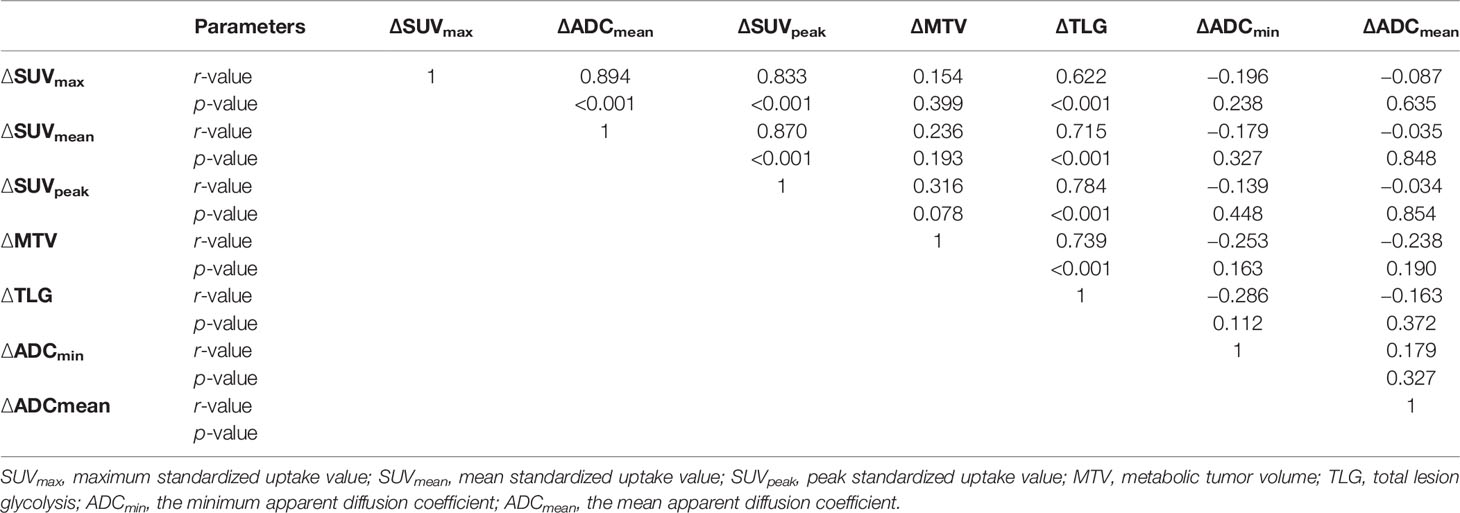

The tumor ADC and SUV values before and during RT showed negligible correlations (pre-RT: SUVmax vs. ADCmin r = −0.322, p = 0.072; SUVmax vs. ADCmean r = −0.217, p = 0.232; SUVmean vs. ADCmin r = −0.258, p = 0.153; SUVmean vs. ADCmean r = −0.256, p = 0.158; dur-RT: SUVmax vs. ADCmin r = −0.133, p = 0.496; SUVmax vs. ADCmean r = −0.133, p = 0.496; SUVmean vs. ADCmin r = −0.013, p = 0.944; SUVmean vs. ADCmean r = −0.121, p = 0.510). There was no correlation between ∆SUV values (∆SUVmax, ∆SUVmean, and ∆SUVpeak) and ∆ADC values (∆ADCmin and ∆ADCmean) (p = 0.238−0.854) (Table 3).

Table 3 Correlation analysis of relative changes in SUV and ADC values before and during radiotherapy.